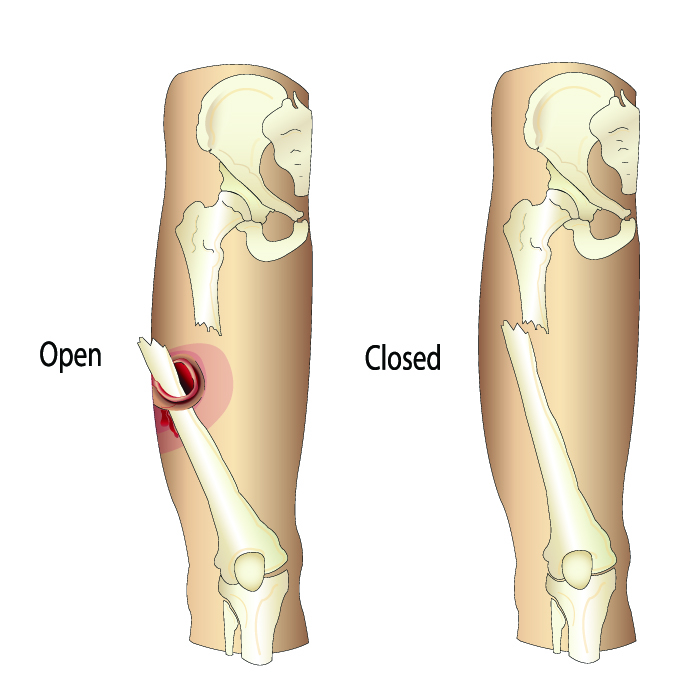

Open (Compound) Fractures

Severe injuries requiring urgent surgical care.